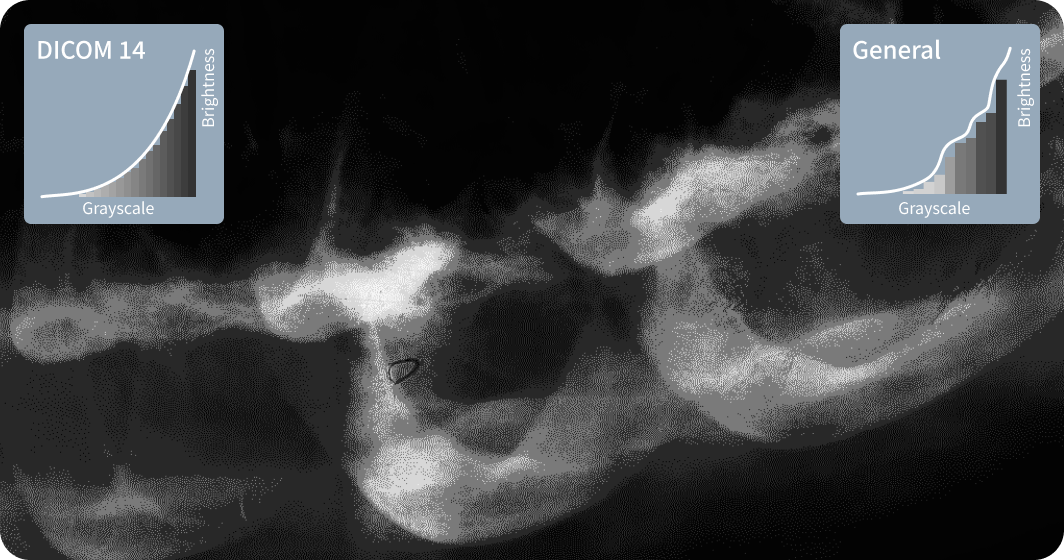

| Compliance with DICOM Part 14 | ✔ |